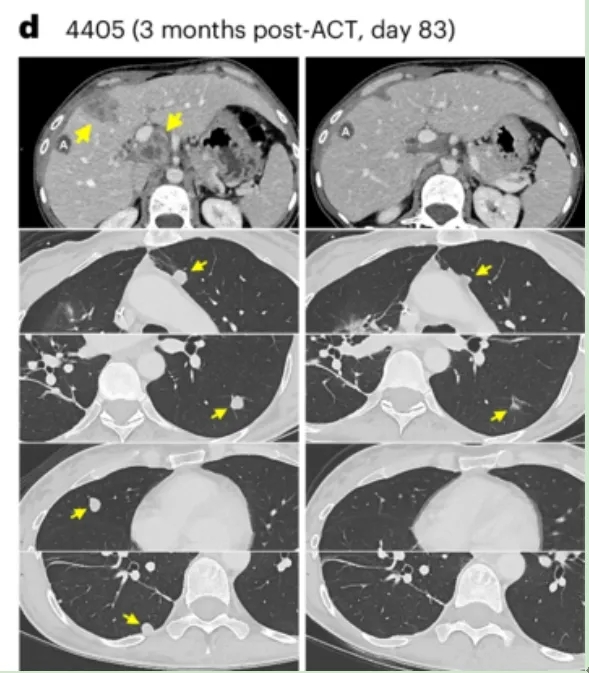

值得一提的是,其中患者4405(转移性直肠癌)在TCR-T细胞回输后,影像学检查显示其肝转移、门静脉淋巴结及多发肺转移病灶均完全消退(详见下图)。

▲图源“Nature Medicine”,版权归原作者所有,如无意中侵犯了知识产权,请联系我们删除